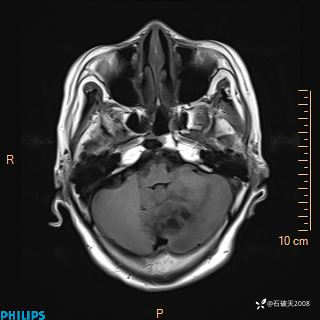

书上说这个肿瘤发生在幕下仅4.09%,你会想到它吗?(病理已公布)

女 86岁 主 诉:乏力1月

现病史:患者1月前活动出现双下肢乏力,无头晕、头痛、恶心、呕吐、肢体活动不利,休息后缓解,间断断发作,症状进行性加重,在家口服药物治疗(具体不详),效差,为进一步诊治,来我院,门诊按“乏力”收住我科,患者自发病以来,神志清,精神稍差,饮食睡眠欠佳,大小便正常,体重未见明显改变。

T2